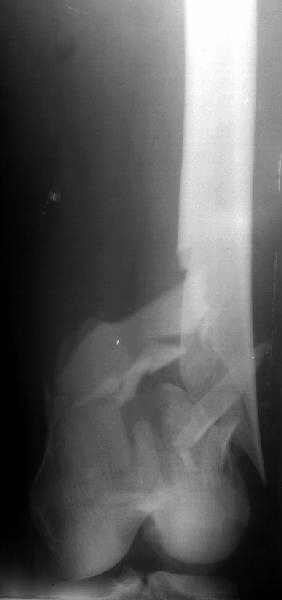

Re: Перелом "около пластинки"

V M Iyer 25 Декабрь 2003, 08:08

AC>>My first thought is closed nailing.

Absolutely right and is the correct way of management. Mobilise him as early as possible.

Nothing special. Encourage him to do all his activities as before. By the way, I do not see any osteoporosis. The fracture of femur, he would have sustained anyway with the fall.